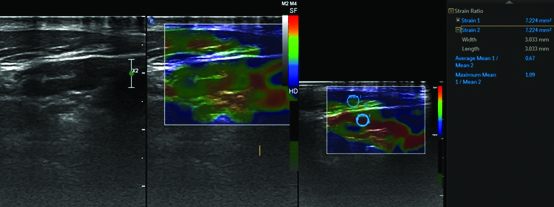

Each patient was subjected to additional real-time elastography examination using the same transducer. For elastography, compression with light pressure followed by decompression was repeated until a stable image was obtained. Five elastography scales were defined: high elasticity (soft): pattern I represented no or very small hard area while at other spectrum pattern V presented where almost whole of lymph node showed hard pattern on strain elastography. Patterns II and III represented hard areas <45% and >45% respectively while pattern IV represented peripheral hard area with central soft area (due to central necrosis). Similar patterns have been defined previously in literature [3,7]. Patterns I and II were considered benign. Patterns III, IV and V were considered to represent malignant lymph nodes. Additional a cine loop of elastography was acquired for calculation of strain ratio using adjacent muscle as reference. For obtaining strain ratio, rounded region of interest was taken at lymph node and at adjacent muscle and thus ratio of their mean elasticity was obtained. A cut-off value of <2 of strain ratio was used to define benign lymph nodes and ≥2 was used to define malignant lymph nodes [Table/Fig-1,2,3,4 and 5]. Final diagnosis of benign versus malignant lymph node was based upon other relevant investigations like FNAC/biopsy findings and/or clinical follow-up after three months.

Showing elastography pattern I in a reactive lymph node with predominantly soft areas (orange/green) and very small hard area (blue). Strain ratio was 0.67.